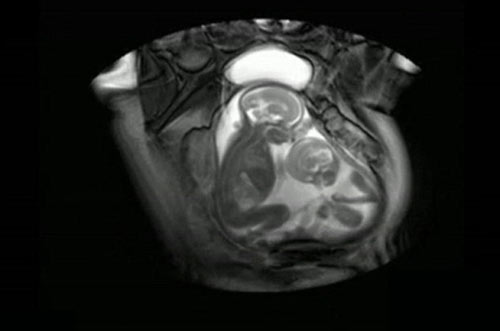

Một đoạn video thú vị vừa mới được công bố cho thấy một cặp trẻ sinh đôi đã đá nhau ngay trong bụng mẹ nhằm giành chỗ để chân. Những hình ảnh tuyệt vời này được ghi lại bởi trung tâm chăm sóc thai nhi Imperial, London bằng thiết bị MRI.

Ban đầu, các bác sĩ tại trung tâm Imperial sử dụng thiết bị MRI để chẩn đoán một hội chứng có khả năng gây tử vong được gọi là hội chứng truyền máu song thai. Hội chứng này chỉ xảy ra ở các cặp song sinh giống hệt nhau khi máu từ một thai nhi này truyền sang cho thai nhi kia.

Hình ảnh cặp song thai trong bụng mẹ. (ảnh minh họa)

Tuy nhiên, trong quá trình chẩn đoán căn bệnh cho cặp song sinh trong đoạn video, các bác sĩ đã phát hiện ra cảnh xung đột khá thú vị giữa hai em bé. Mời các mẹ cùng theo dõi.